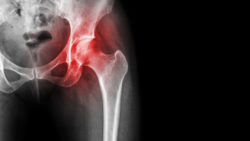

Arthritis at hip joint . inflamed of hip joint, Avascular necrosis.Many individuals discover that as they age, their joints present problems. They often have to undergo joint replacement surgery in order to relieve pain or to do basic things such as walk or exercise. Hip replacements specifically can help restore motion to those who have lost mobility.

A hip replacement system is made up of three basic parts: a stem implanted into the femur (the bone in the thigh), a ball that attaches to the top of femur (called the femoral head) and the cup that the ball rests in (which is attached to the pelvic bone).

As a person moves their joint or walks, this “ball” moves in the “socket” that is attached to the pelvis.